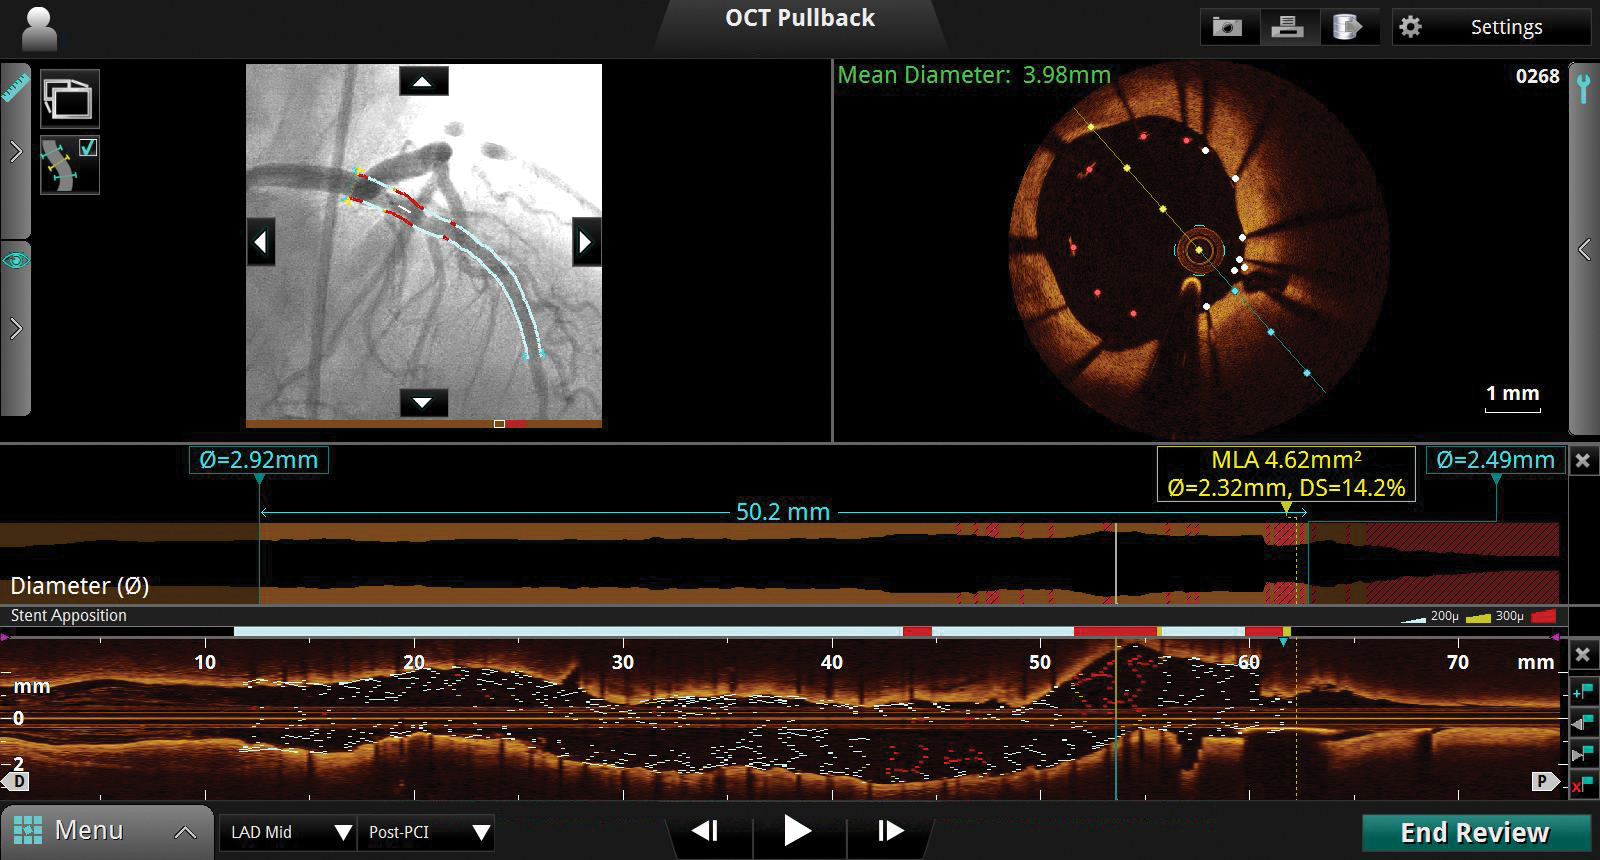

In a clinical trial, medical device maker St. Jude Medical (St. Paul, MN) has demonstrated that percutaneous coronary intervention (PCI) guided by optical coherence tomography (OCT) is superior to angiography in stent expansion and procedural success, and non-inferior to intravascular ultrasound (IVUS) guided-PCI in post-procedure minimal stent area (MSA).

The study findings confirm that OCT-guided PCI results in comparable MSA and stent expansion as IVUS-guided PCI; significantly greater stent expansion than angiography-guided PCI, with greater rates of procedural success; and is superior to IVUS-guided PCI at detecting predictors of major adverse events (major stent malapposition and dissection).

During PCI procedures, physicians use diagnostic imaging to make decisions related to stent sizing and to assess how to best keep the artery expanded to restore blood flow to the heart. A key factor in reducing stent failure is increasing the MSA and securing appropriate stent expansion during PCI to restore blood flow, a process commonly known as revascularization.

In the ILUMIEN III study, physicians employed the St. Jude Medical OPTIS Integrated and ILUMIEN OPTIS PCI optimization systems, along with the Dragonfly imaging catheters designed for high-resolution imaging, to assess vessel and lesion characteristics, size stents, and optimize stent placement in patients randomized to OCT-guided stent implantation.